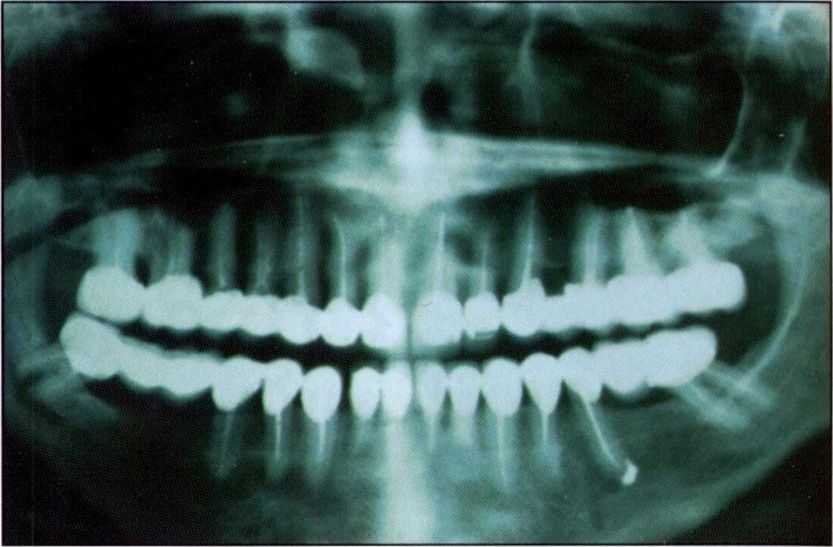

На рис. 1 хорошо видны некоторые из перечисленных осложнений. Подобные осложнения приводят через какое-то время после фиксации протезов к необходимости перелечивания зубов, что иногда требует снятия зубных протезов и повторного протезирования.

| Рис. 1. «Жертва» металлокерамики |